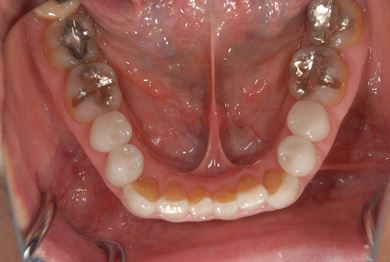

セラミックの症例写真 SHINBI

セラミック治療+ラミネートベニア治療

| 主訴 | 虫歯を白い詰め物で治療したい。全体的に歯の色が気になるので、ホワイトニングをしたい。ホワイトニングの効果がなければ、セラミック治療を受けたい。 | ||||||||||||||||||||||||||||||||

| 治療方針 | セラミック治療にて、審美的回復を行う。 | ||||||||||||||||||||||||||||||||

| 治療内容 | ジルコニアオールセラミッククラウン1本(オールセラミック用土台1本)、オールセラミッククラウン9本(オールセラミック用土台1本)、オールセラミックラミネートベニア11本 | ||||||||||||||||||||||||||||||||

| 総治療費 | 2,893,275円 | ||||||||||||||||||||||||||||||||

| 治療期間 | 10ヶ月 |